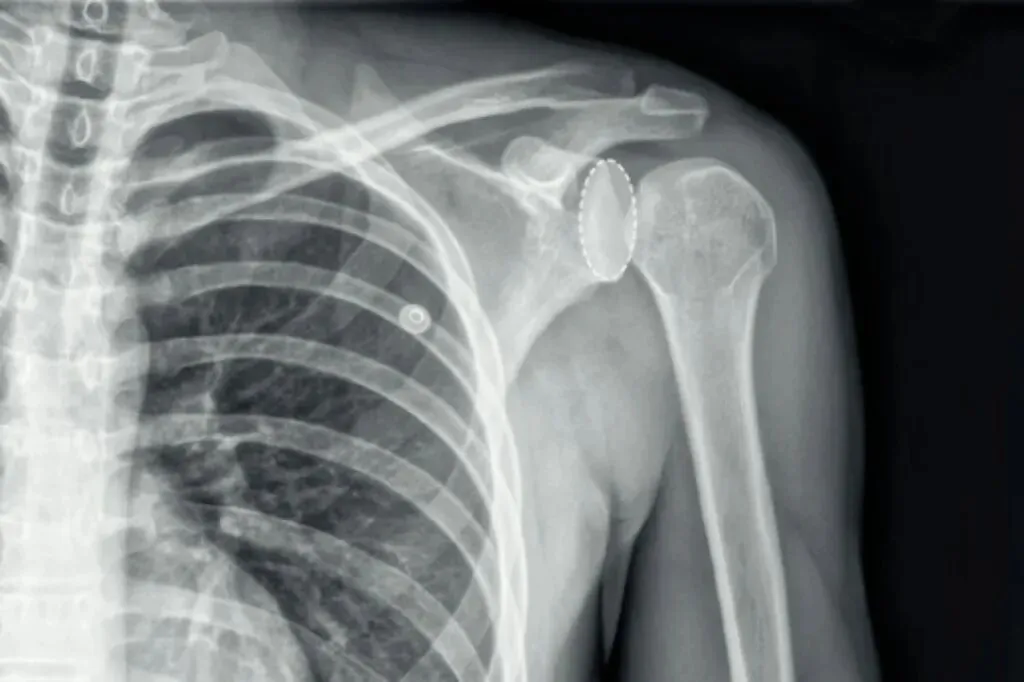

灯泡征是指在肩关节正位X线中存在后脱位可能的影像学表现。由于肱骨近端内旋,肱骨头的形态变圆,呈灯泡状,所以称为灯泡征。

但灯泡征并不能完全确定肩关节是否后脱位,还需结合其他影像学征象,如槽线征、环征,当然也要结合临床症状及体征等综合判断。下面小编带你学会如何观察这几个影像学征象。

常可伴肱骨内旋,肱骨头投影变圆呈灯泡征。肱骨内旋后,大小结节投影有时候会形成一条折线,称M字征。

需要注意在肩关节正位摄影体位不标准,肱骨不能外旋的情况下,也会出现M字征。